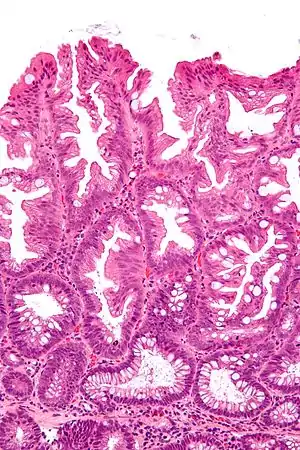

Villous adenoma

These adenomas may become malignant (cancerous). Villous adenomas have been demonstrated to contain malignant portions in about 15–25% of cases, approaching 40% in those over 4 cm in diameter.[7] Colonic resection may be required for large lesions. These can also lead to secretory diarrhea with large volume liquid stools with few formed elements. They are commonly described as secreting large amounts of mucus, resulting in hypokalaemia in patients. On endoscopy, a "cauliflower' like mass is described due to villi stretching. Being an adenoma, the mass is covered in columnar epithelial cells.